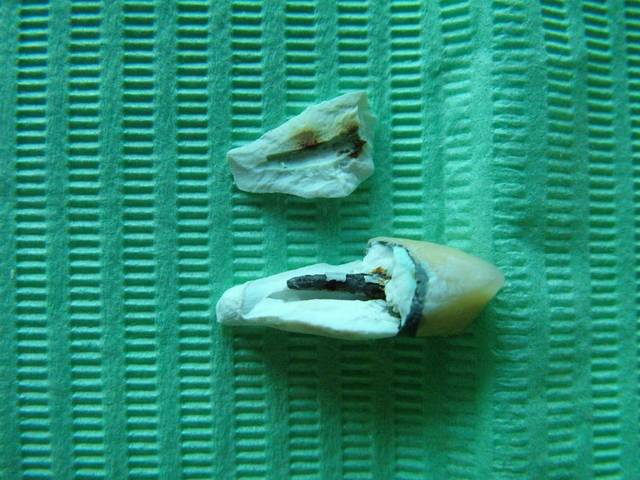

D'accord, mais ce qui me dérange, ce sont les images de corrosion, alors que tout a été réalisé sur métal précieux.

D'ou vient la corrosion?

On voit sur le tenon, et sur le bandeau périphérique lingual, des piqures qui en sont le signe.

Mais ici, sur le tenon et sur le bandeau, on voit des petits cratères. Donc électrosoustraction, c'est bien ce qui me dérange.

Que mon bridge se corrode, je veux bien l'admettre, mais l'I.C. !!!!!!!!!!! C'est une corrosion dans la masse, ni le ciment de scellement, ni la pâte à canaux n'ont isolé de la corrosion.

Un canal secondaire ? en relation directe avec l'IC

ou bien un début de fêlure puis fracture avec infiltrations conséquentes avant depistage du pb?

Tu sembles décrire une corrosion par piqures qui montre une attaque acide au niveau des joints de grain de ton alliage.

La corrosion sur un tel alliage précieux ne me semble pas très courante. En tout cas, elle me laisse circonspect, mais avoir une telle corrosion sur un tel alliage me fait penser à un problème qualitatif de l'alliage employé. Car même sur de nombreux alliages non précieux, je ne peux pas dire avoir vu des milliers de corrosion par piqures.

Es tu sûr que ton protho ne te fais pas tes IC en surcoulée sans te le dire. Je connais un protho qui fait cela car ses clients ne lui fournissent pas le tenon calcinable et il utilise le pivomatic de l'empreinte pour faire l'IC. Ou alors, il ne met pas un pourcentage d'alliage neuf pour ses coulées.

Il s'agissait d'un tenon injecté.

Je pense que tu as peut etre raison quand tu évoque la possibilité d'un inlay core dans un autre alliage que celui du bridge.

Les habitudes sont difficile à changer, et j'ai du heriter d'un I.C. en Or blanc.

en effet la photo montre de l'arrachement dentinaire

Je pense que la longueur du bridge est le premier facteur responsable de la fracture de la racine.

Il est possible aussi que cela ait commence par une simple felure avec colonisation de la racine,puis elargissement du trait de fracture jusqu'a "explosion" de la racine.